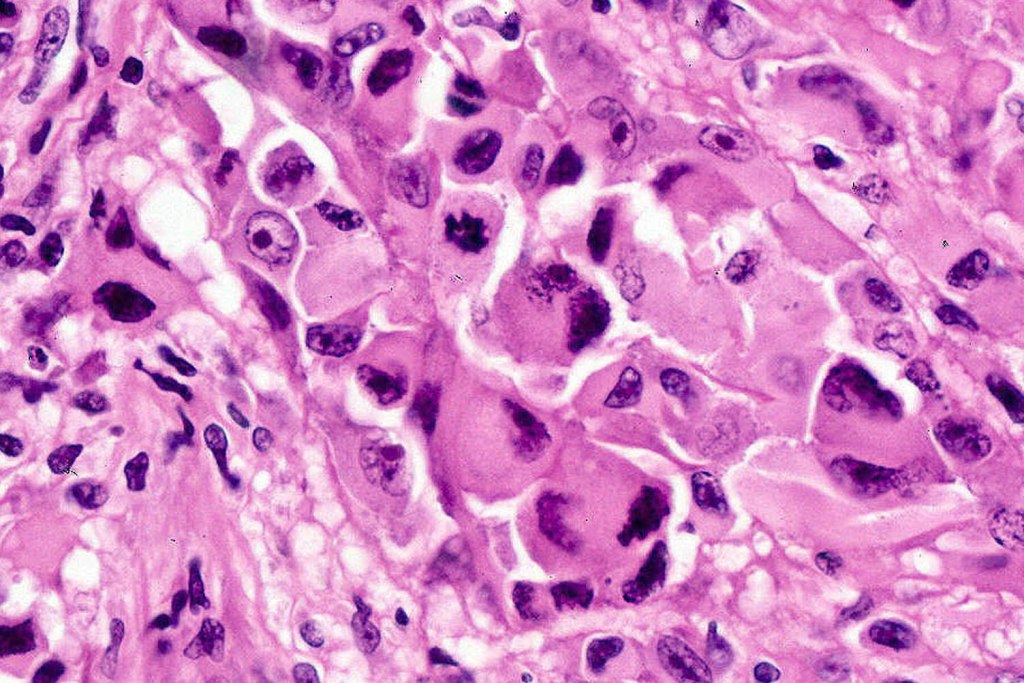

•Characterized by pleomorphic tumor cells with large eosinophilic, hyaline globular inclusions and eccentric vesicular nuclei containing prominent nucleoli, mitoses often conspicuous

•Inclusions predominantly composed of vimentin intermediate filaments

•Vimentin & sometimes desmin expression positive in the inclusions